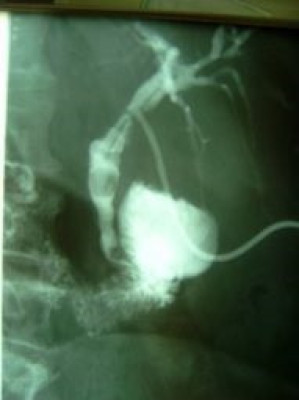

Extracción percutánea de cálculo de coledoco

Envíado por Dr. Carlos Miguel Zavaleta Consuegra